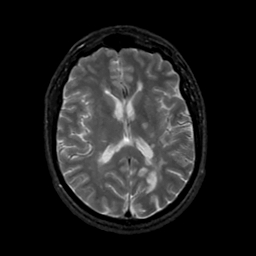

MR Study #17, July 7, 1991 -- Slice #28